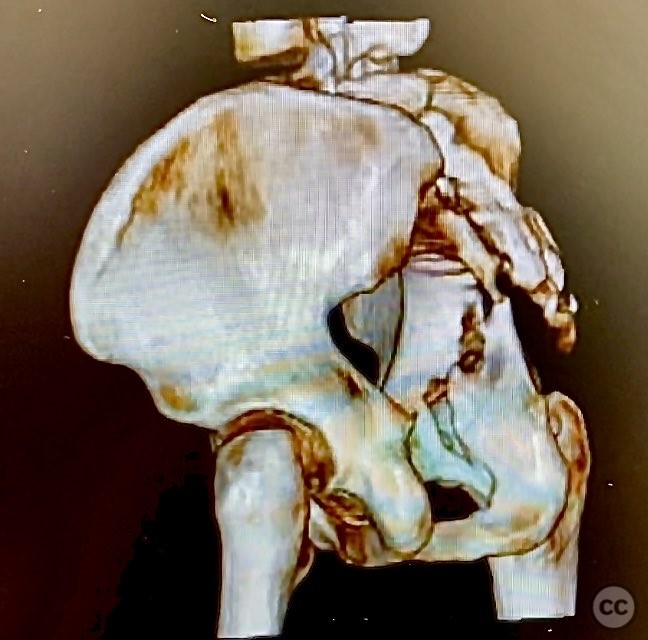

Clinical and radiological findings:  The patient is morbidly obese and sustained an unstable, displaced posterior column/posterior wall (PC/PW) acetabular fracture. Axial computed tomography images revealed a 2x2x1.5 cm pyramidal chondrocancellous articular fragment wedged in the fracture plane near the incisura ischiadica major (greater sciatic notch). Surface-rendered reconstructions further delineated the fracture morphology and fragment position. Obesity was noted to complicate all aspects of management, including anatomical localization, intraoperative imaging, and soft tissue handling.